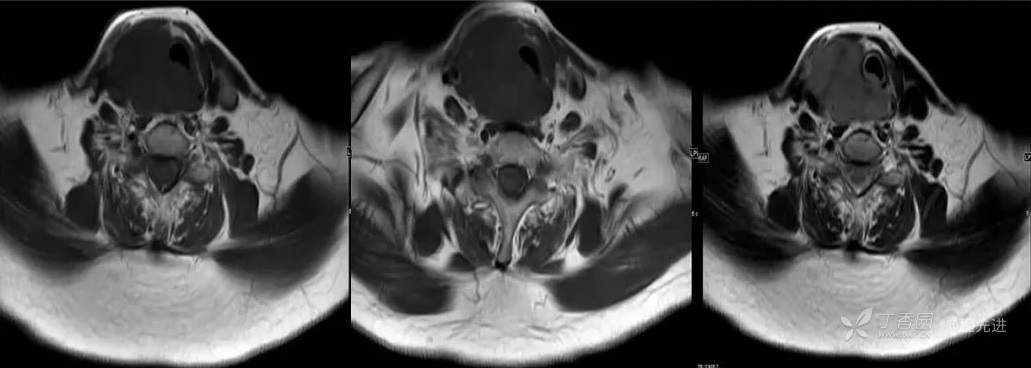

MR

T1

T2